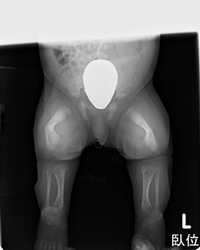

遺伝子の病気で正常な骨を作れない病気で全身の骨の変形が生じて重症例では命にかかわります。

患者も国内に100-200人程度と言われていて非常に稀な病気です。